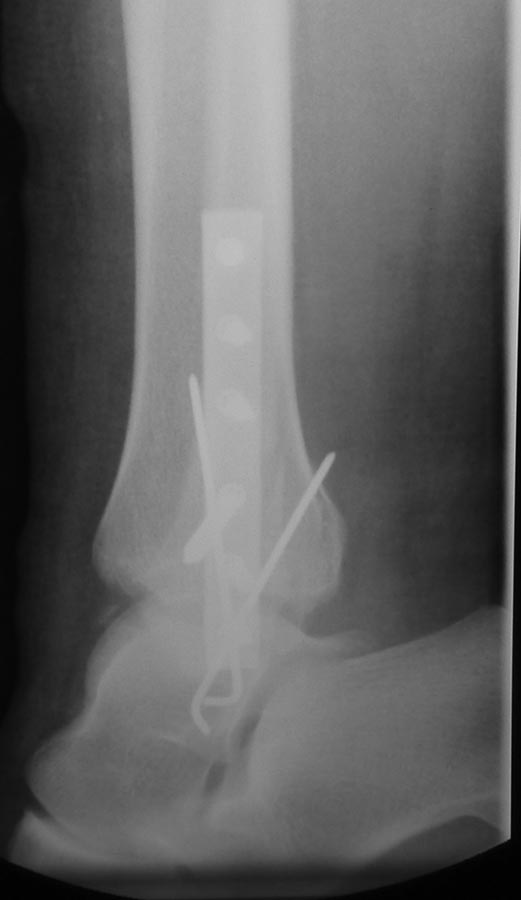

Девушка 30 лет была прооперирована через несколько часов после травмы

(до- и послеоперационные снимки представлены). До операции обращали на

себя внимание выраженный дефицит тыльного сгибания другой стопы и

обширные натоптыши под головками центральных плюсневых костей на обеих

стопах. При сгибании коленного сустава сгибание со значительным

усилием в голеностопном суставе на здоровой стопе едва достигало 90 гр.

Такой же объем движений был выявлен и на операционном столе на

травмированной ноге после выполненияостеосинтеза. Раньше, несмотря на